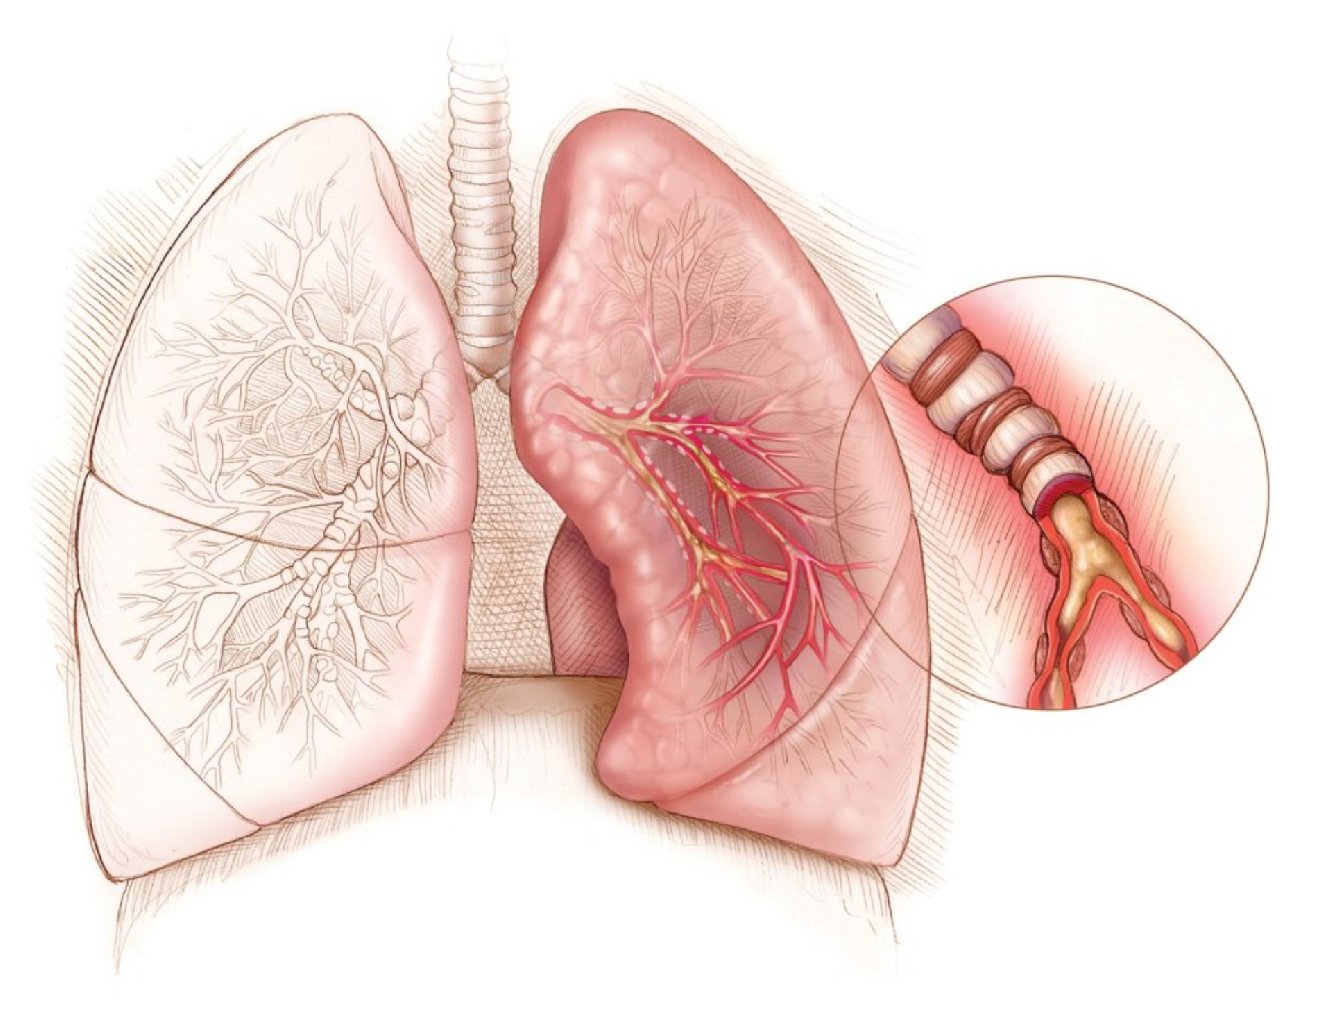

Ağciyər emboliyasının ən çox görülən səbəbi ayaq damarlarında meydana gələn dərin ven trombozu (DVT) ...

Səbəblər: Uzun müddət hərəkətsiz qalmaq (məsələn, uzun müddətli uçuşlar və ya yataq istirahəti) ...